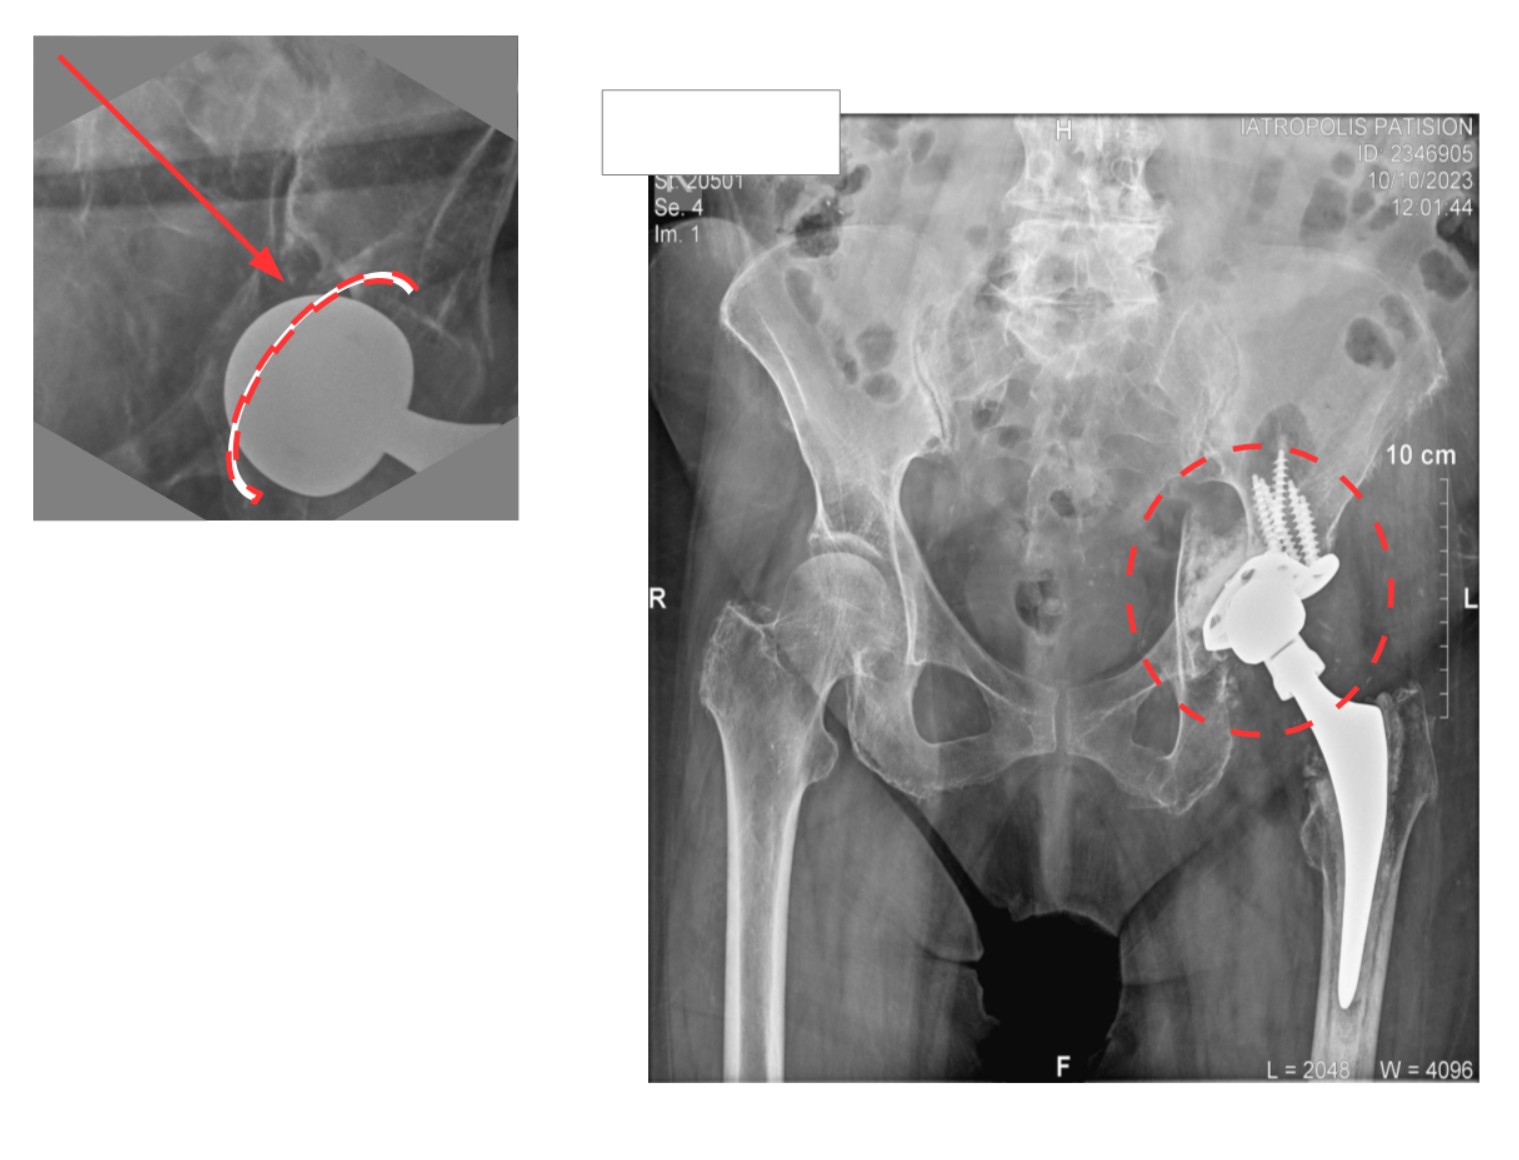

Στις εικόνα 11 και εικόνα 12 ημιαρθροπλαστική AMIS για υποκεφαλικό κάταγμα ισχίου, από προσωπικό αρχείο

Χωρίς ικανή εμπειρία, επιπλοκές μπορεί να συμβούν: στην εικόνα 13, στην αριστερή πλευρά ημιαρθροπλαστική AMIS στην οποία τοποθετήθηκε ολόκληρος ο στυλεός του μηριαίου εκτός του αυλού. Ο ασθενής κινητοποιήθηκε την επομένη με αφόρητο πόνο σε εξάρθρημα. Όσο κι αν φαίνεται απίθανο, είναι μια επιπλοκή που μπορεί να συμβεί σε μη έμπειρα χέρια. Δεξιά στην εικόνα φαίνεται ο ορθός τρόπος τοποθέτησης του στυλεού.

Στην εικόνα 14, κατά τη διάρκεια ημιαρθροπλαστικής AMIS, η απειρία οδήγησε σε εργώδεις προσπάθειες ανάταξης και κάταγμα κοτύλης. Αντιμετωπίστηκε στην κλινική μας με ειδικού τύπου πρόθεση κοτύλης του τύπου της αναθεώρησης αρθροπλαστικής (revision hip arthroplasty)